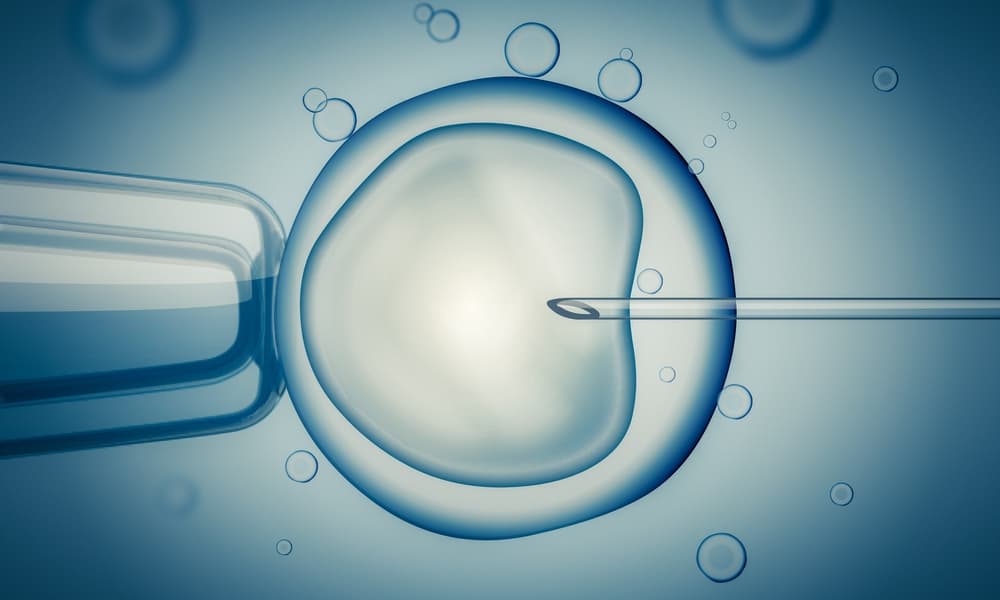

La mayoría de las caries tiene un origen bacteriano y, desde hace años, se trabaja en desarrollar una vacuna que nos haga inmunes a ellas. Científicos del Instituto Forsyth en los Estados Unidos, desarrollaron una vacuna contra la Streptococcus mutans, la bacteria responsable de la mayor cantidad de infecciones dentales.

Esta vacuna, haría que el sistema inmune pueda fabricar anticuerpos que eliminen las enzimas que permiten que la streptococcus mutans se adhiera a los dientes. Si esta bacteria no puede pegarse a los dientes, se queda en la saliva para luego ser desechada.

La vacuna, que ya fue probada en animales, está mostrando resultados promisorios y se cree que en poco tiempo estaría disponible para su uso directo en personas. Si le tienes miedo a las agujas no te preocupes, ya que hasta podría administrarse mediante gotas nasales.